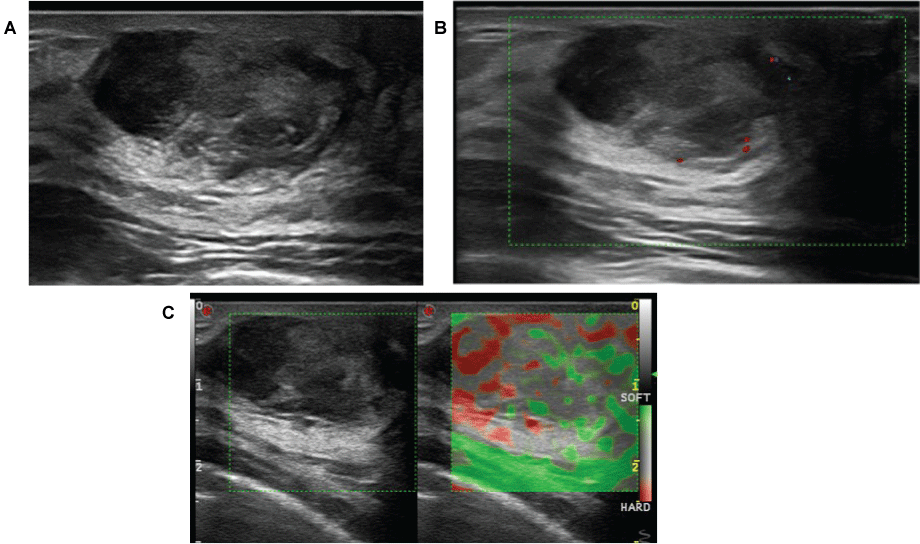

Further evaluation included mammography and ultrasonography (US). Mammography demonstrated a 2.5 cm oval mass, with circumscribed margins. US showed a solid mass, oval and circumscribed. The eco pattern was heterogeneous, showing hypo and hyperechoic areas, suggesting fat containing lesion. No vascularity was found with Doppler. Elastography demonstrated soft stiffness. Posteriorly, tomosynthesis was performed and no fat was found in the lesion. In face of these findings, core biopsy was executed and demonstrated diffuse large B-cell lymphoma (Figure 1 and Figure 2).

Figure 2: B mode US demonstrates (a) solid mass, oval and circumscribed, heterogeneous, with hypo and hyperechoic areas, suggesting fat containing lesion. Doppler (b) showed no flow and elastography (c) demonstrated soft stiffness.